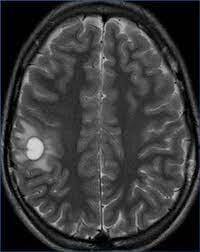

Se pueden apreciar _______ en T2 y FLAIR.

¿Qué hallazgos en RM se pueden encontrar en la esclerosis múltiple,?